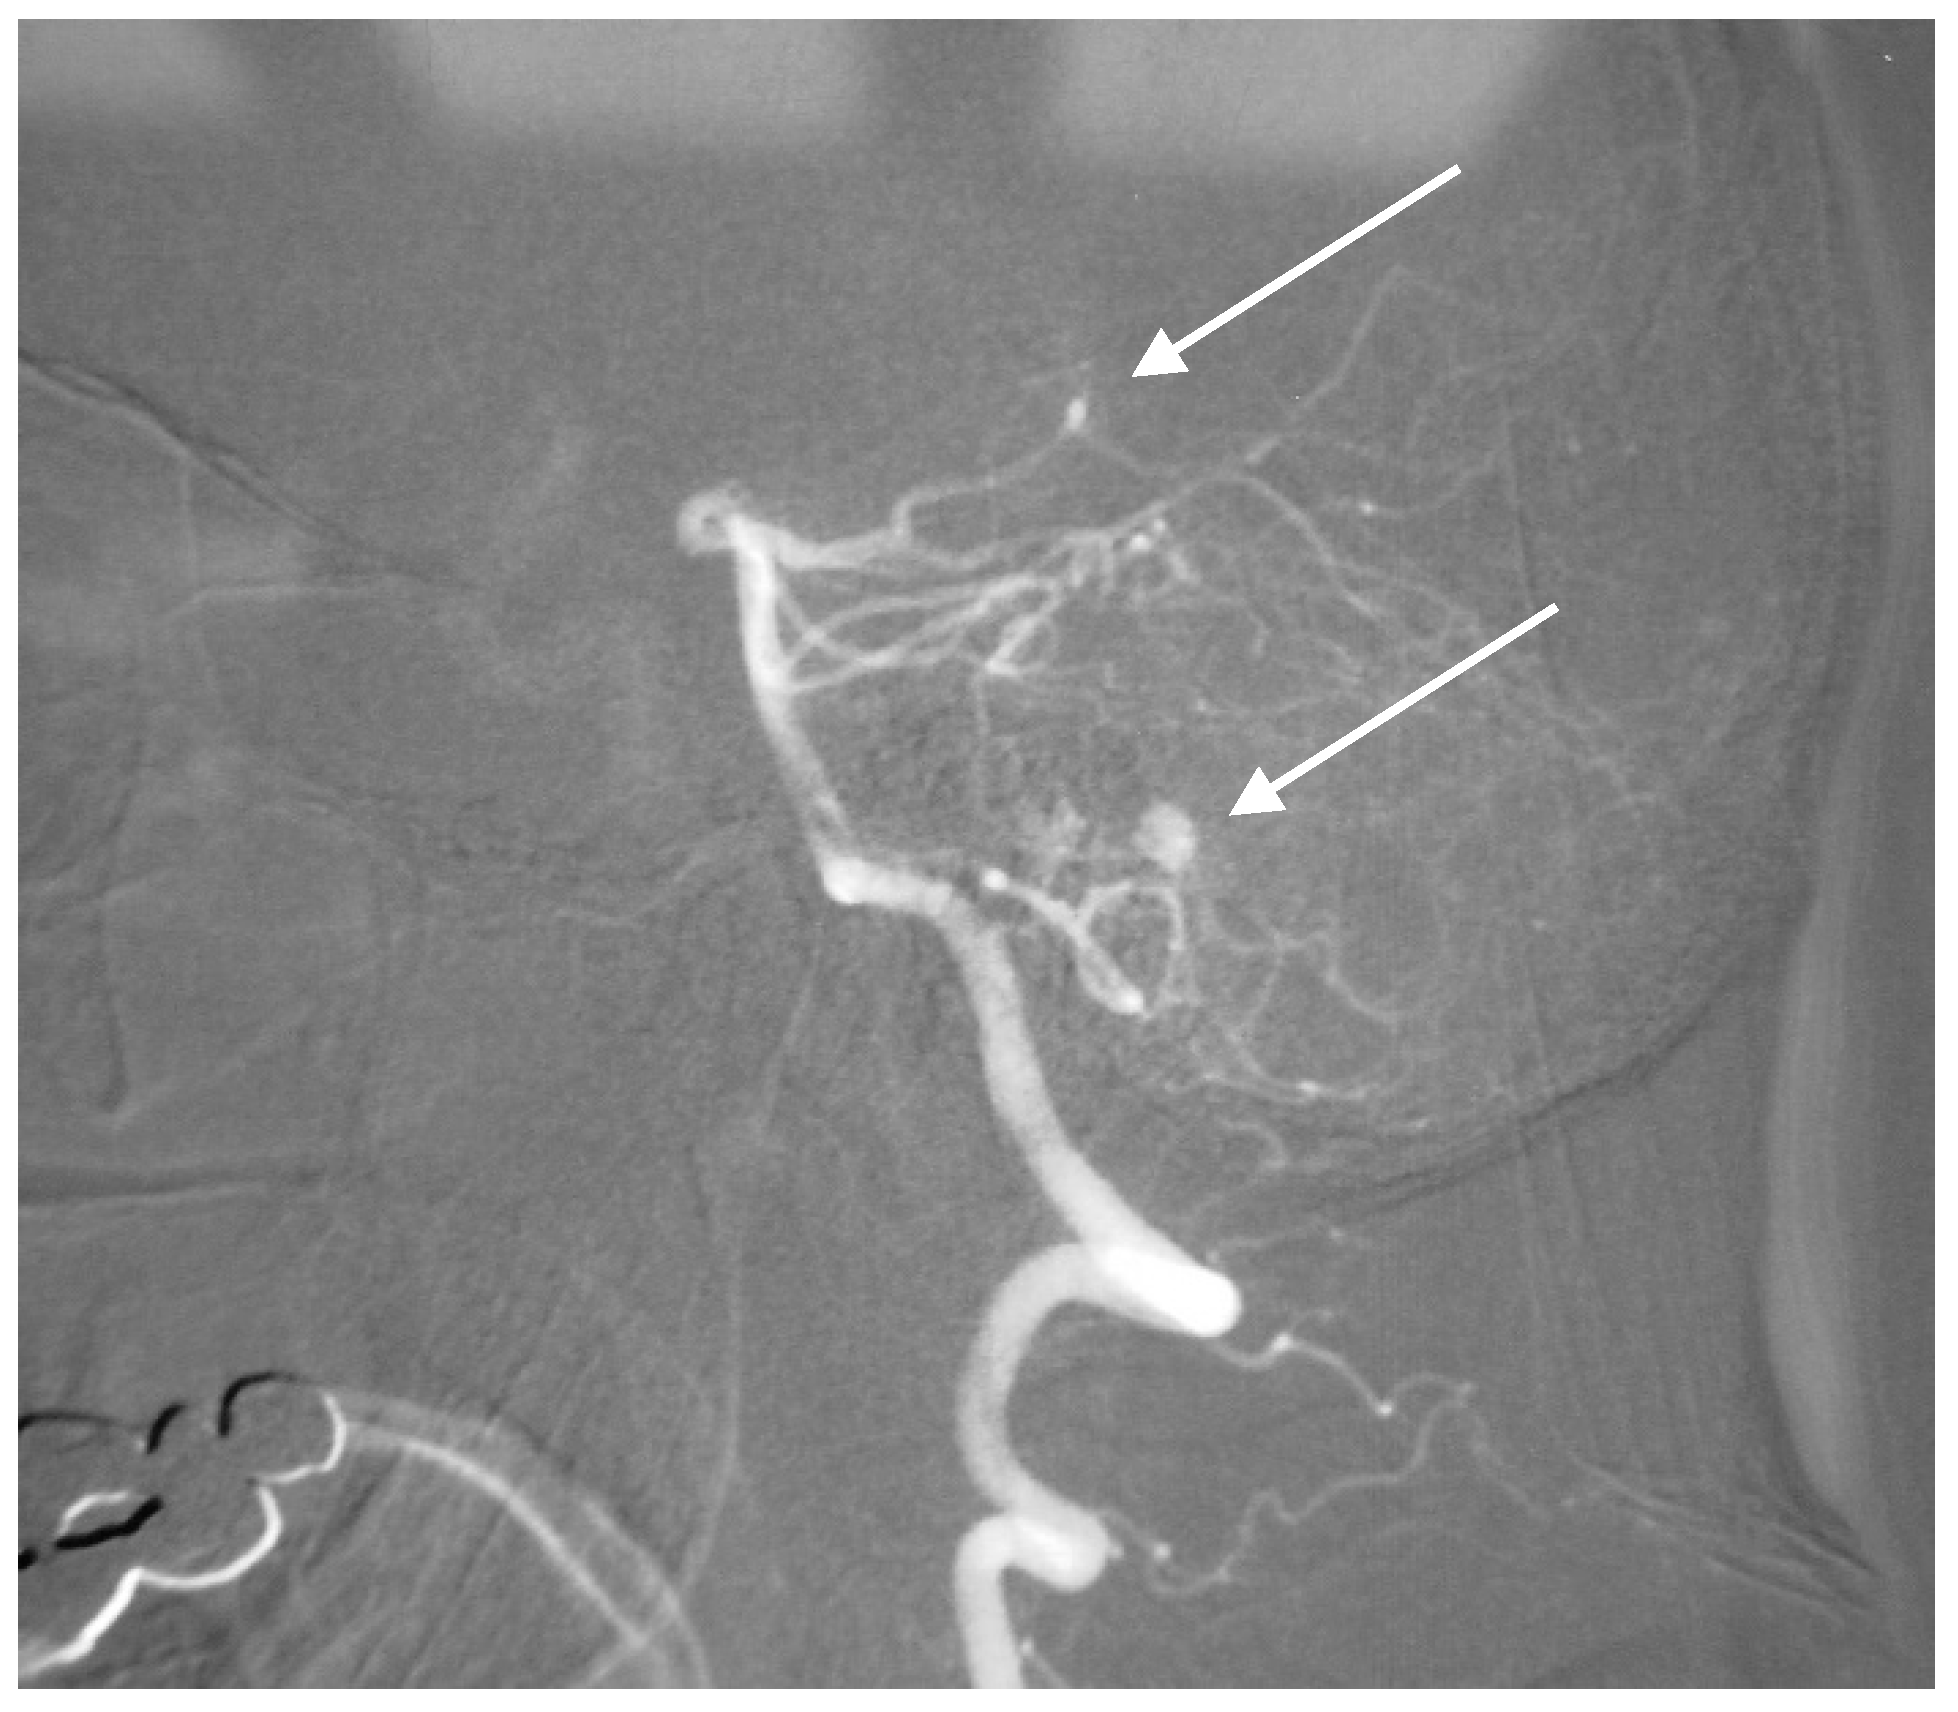

2.6. SCA Aneurysms and AVM

A 58-year-old woman with sudden onset of headache and vomiting was admitted to hospital. The CT scan showed subarachnoid hemorrhage (Fischer grade 3), and the CT angiogram revealed AVM with an associated aneurysm on the left superior cerebellar artery (Figure 9). Endovascular treatment was indicated, and successful Onyx embolization of AVM and coil embolization of the aneurysm was performed (Figure 10). The postoperative course was also without complication, and the patient is followed up.

Figure 9. Computer tomography angiography with aneurysm of the left SCA associated with cerebellar AVM.